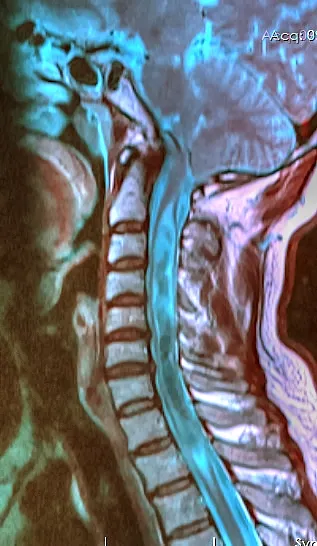

La síndrome de Chiari és una malformació congènita o adquirida en què una part del cervell, les amígdales cerebel·loses, es desplacen cap avall, entrant dins del canal espinal. Això pot provocar compressió sobre la medul·la espinal i dificultar la circulació del líquid cefaloraquidi.